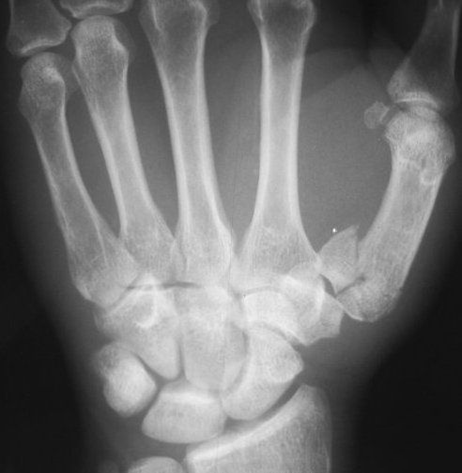

(7)Boxer 骨折

拳击骨折:指第5 掌骨颈骨折,伴有掌骨头向掌侧移位,骨折端背侧成角,多发生于握拳击打损伤所致,同样的损伤机制,第 4 掌骨颈部骨折,也称 Boxer 骨折。